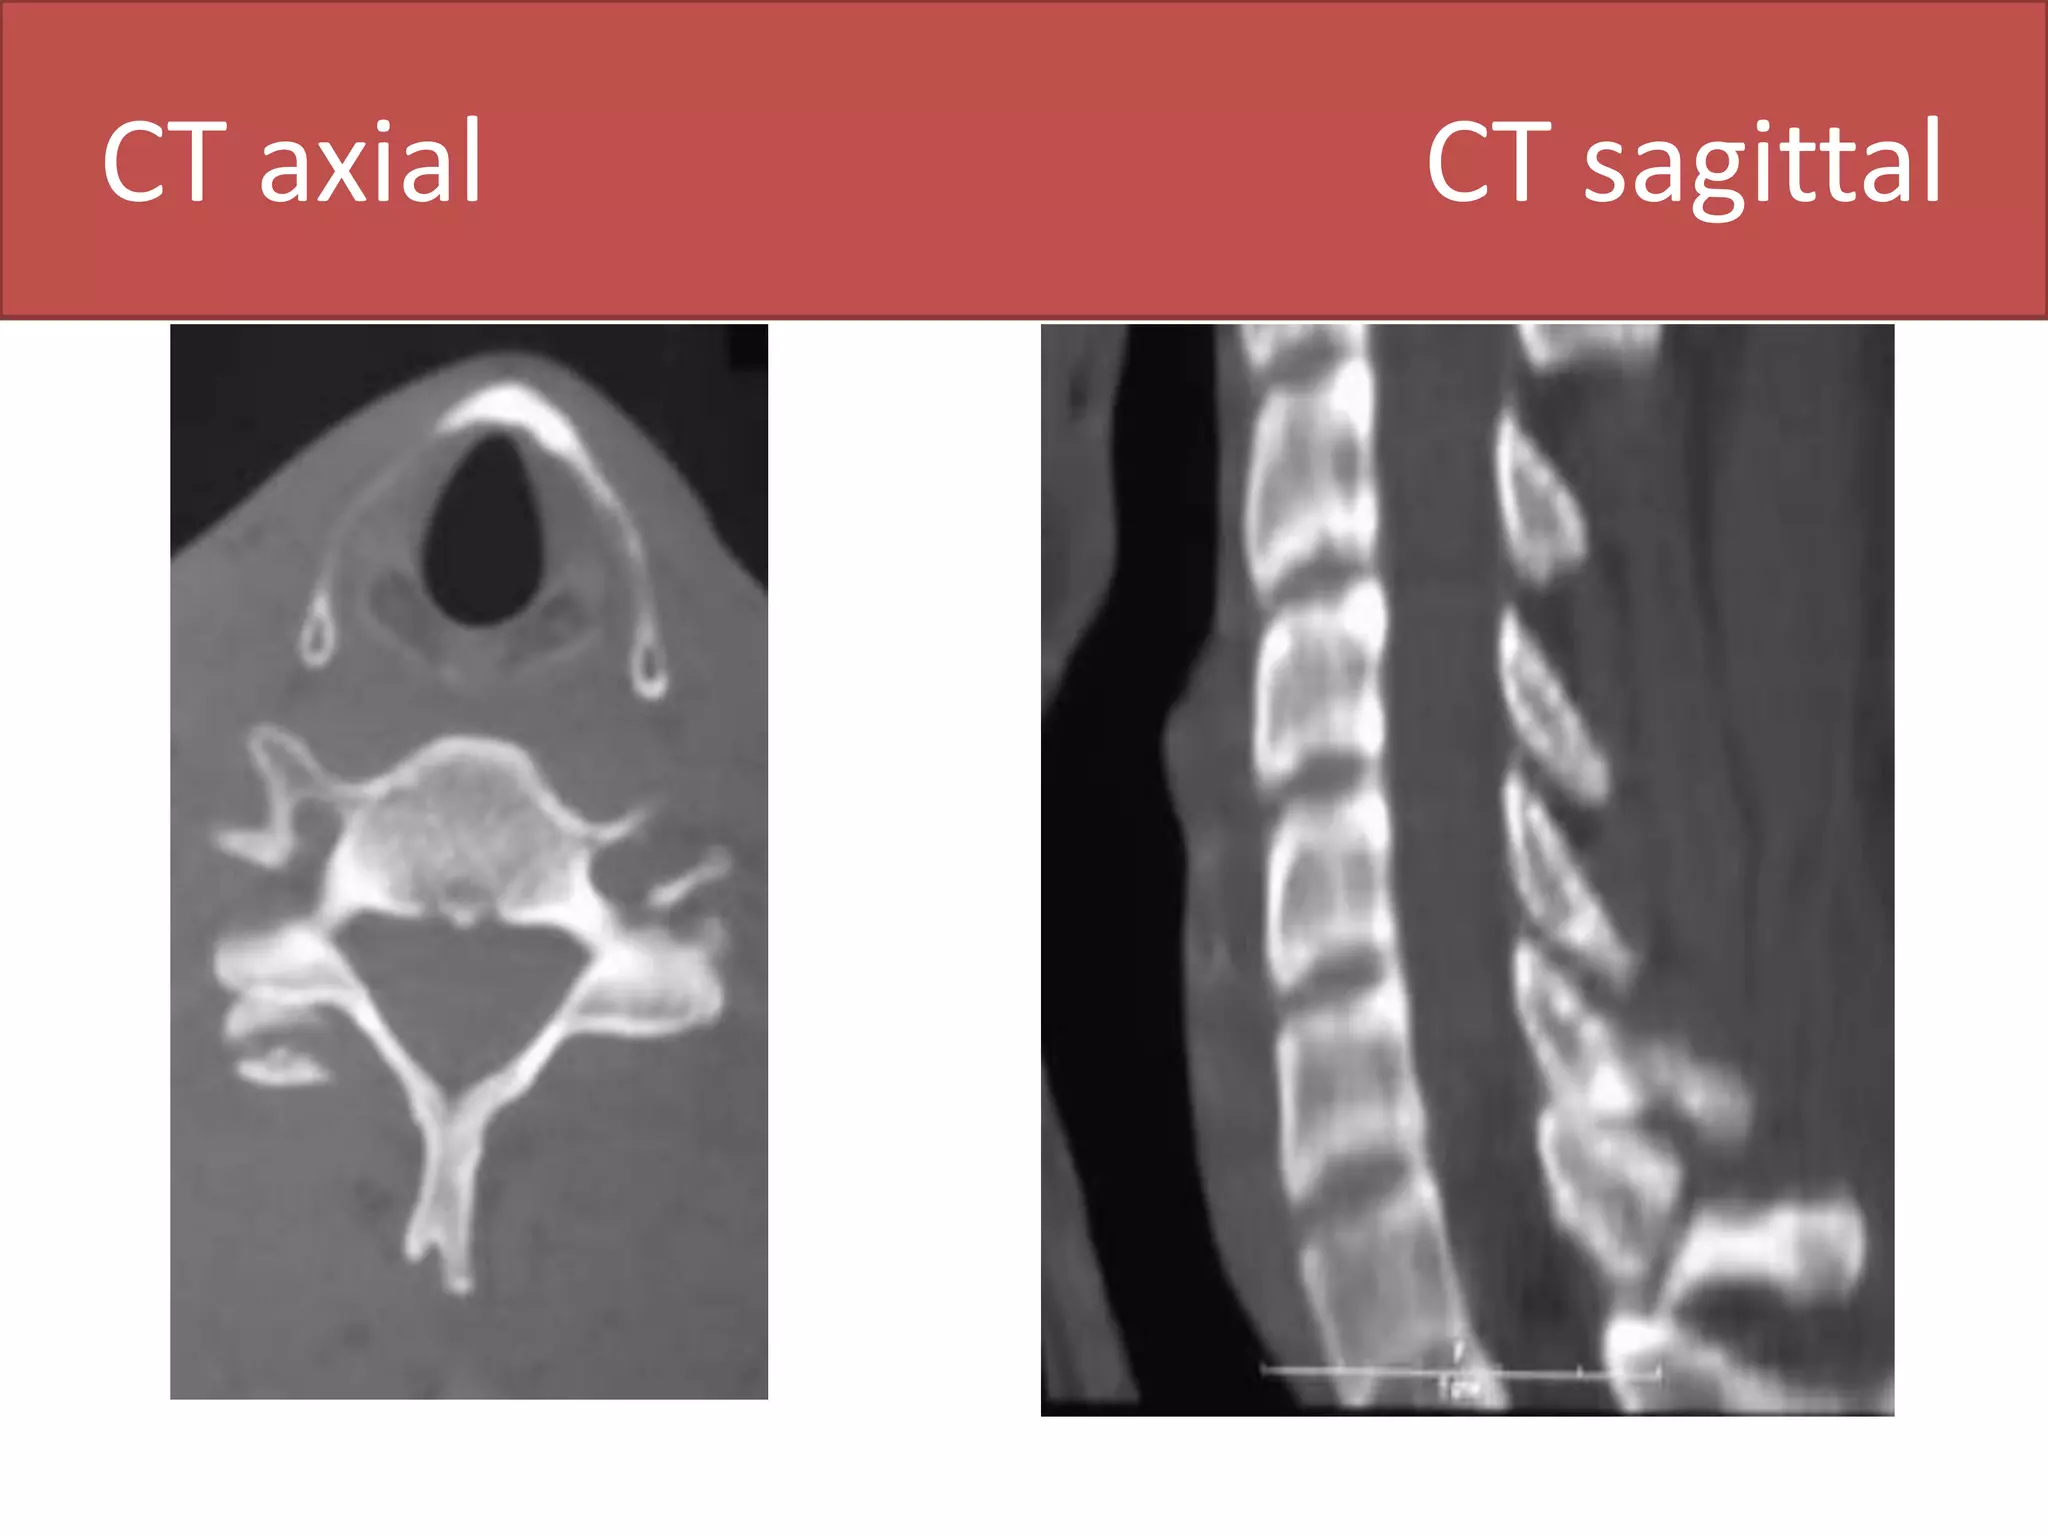

CT axial                                 CT sagittal